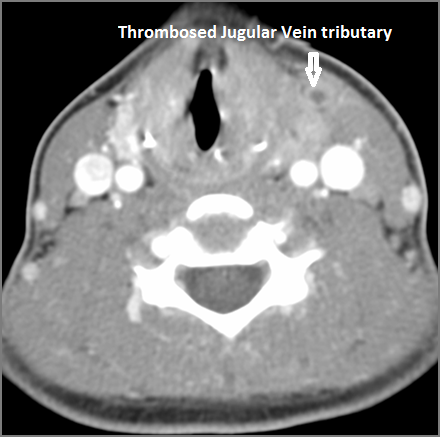

Vascular Findings

There is evidence of thrombus, thrombophlebitis or other occlusive or inflammatory process of the jugular vein or smaller venous tributaries. [Yes/No]

There is evidence of thrombus, thrombophlebitis or other occlusive or inflammatory process smaller jugular venous tributaries. [Yes/No]